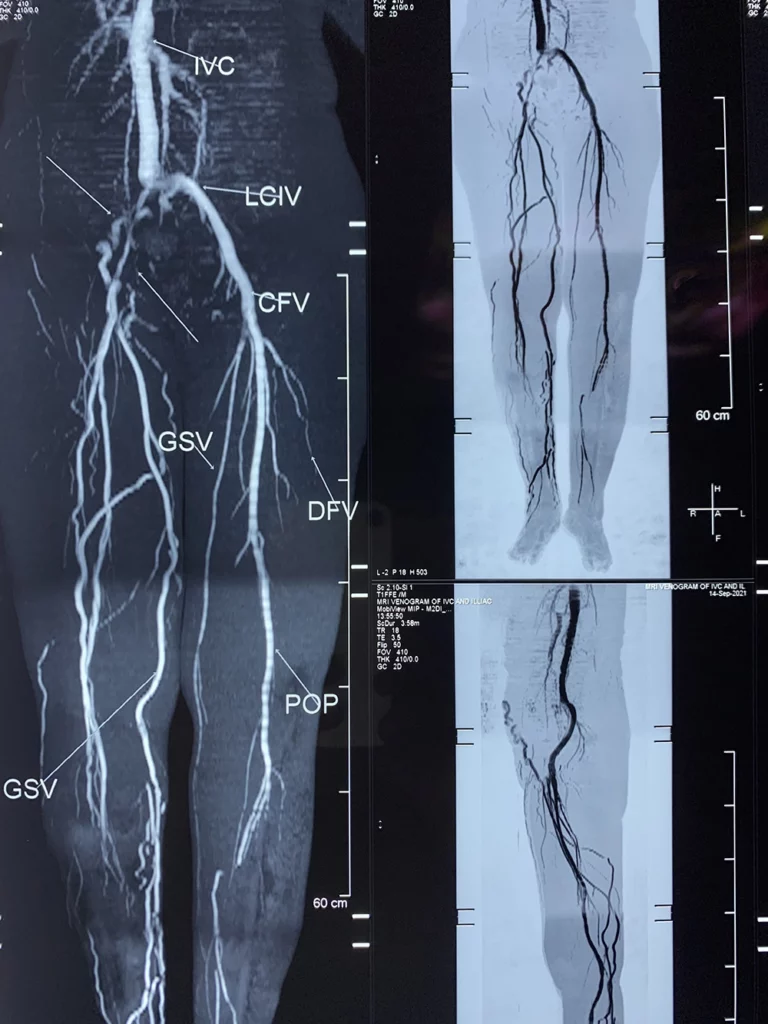

The post thrombotic syndrome is the most important late complication of acute Deep Vein Thrombosis, and it is responsible for a greater degree of chronic socioeconomic morbidity. Five years after Iliofemoral deep venous thrombosis (DVT) treated conservatively with anticoagulation, 90% of patients suffer symptoms of chronic venous disease. Following Deep vein thrombosis in lower limbs, Only approximately 20% of Iliac veins will completely recanalize with anticoagulation treatment. The remaining veins will recanalize only partially and develop varying degrees of obstruction and collateral formation in both Common Iliac and External Iliac vein segments.

Late presentations of patients with Post thrombotic syndrome with Chronic symptoms in lower limbs like Pain, edema, non healing venous Ulcers are treated with Iliocaval Balloon Venoplasty and Stent Placement. Following stenting patients are managed medically by Vascular Surgeon with regular follow-up.